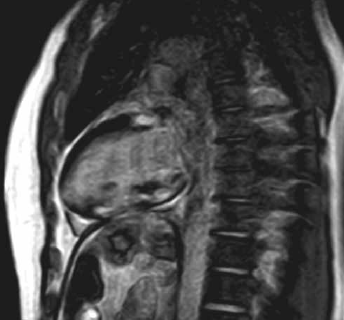

Se solicitó una resonancia magnética nuclear (RMN) cardíaca que mostró hallazgos compatibles con enfermedad infiltrativa, observándose edema miocárdico difuso, que luego del realce tardío con la inyección de gadolinio evidenció áreas de fibrosis focal abarcando segmentos subepicárdicos, intramiocárdicos y suben-docárdico (Figuras 3 y 4).